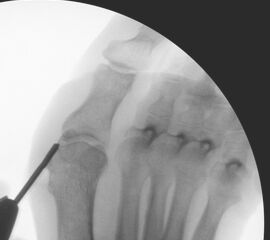

• Positionierung des Bildverstärkers im 90° Winkel zur Fußlängsachse (Abbildung 4).

Die Fräse wird auf eine Drehzahl von 3000 – 5000 RPM eingestellt.